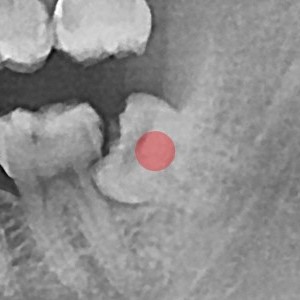

사랑니발치 30대/여성